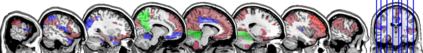

In this paper, we propose methods for functional predictor selection and the estimation of smooth functional coefficients simultaneously in a scalar-on-function regression problem under high-dimensional multivariate functional data setting. In particular, we develop two methods for functional group-sparse regression under a generic Hilbert space of infinite dimension. We show the convergence of algorithms and the consistency of the estimation and the selection (oracle property) under infinite-dimensional Hilbert spaces. Simulation studies show the effectiveness of the methods in both the selection and the estimation of functional coefficients. The applications to the functional magnetic resonance imaging (fMRI) reveal the regions of the human brain related to ADHD and IQ.